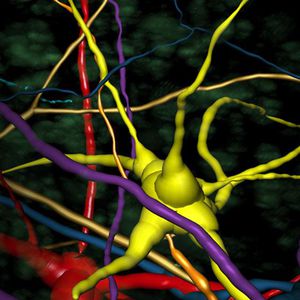

... El paquete Imaris for Neuroscientists permite la reconstrucción 3D de neuronas y el análisis de arborización. Puede resolver diversas estructuras, como axones y dendritas, somas, espinas dendríticas, microglía o astrocitos. Calcula una ...